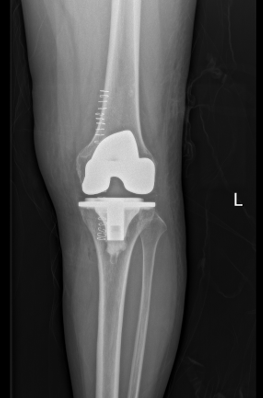

术后关节力线恢复